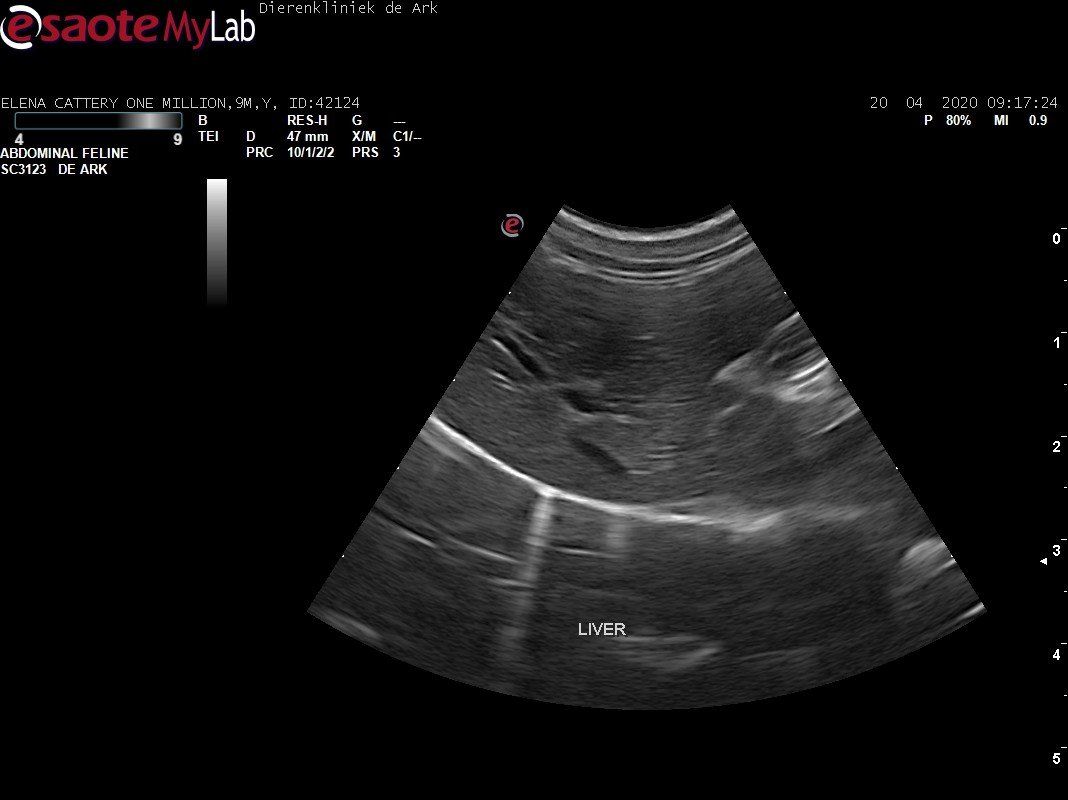

3,200 kg , echo en nieuw bloedonderzoek gedaan wat perfect ging door middel van gapabetine

Voor de garanties en om recht te hebben op medicatie bij herval eist Mutian diverse onderzoeken en controle momenten. Dit zijn bloedonderzoeken maar ook zoals hieronder te zien is echo's. Elana is volledig gecontroleerd op afwijkingen, gelukkig waren de echo's goed.